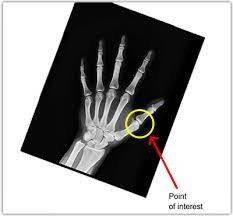

The most urgent need for AI in biomedicine is in the diagnostics of diseases. AI allows health professionals to give earlier and more accurate diagnostics for many kinds of diseases [10]. Propper image processing, appropriate selection of features, and AI methods can support medical diagnostics. This topic has been the subject of much research in recent years. One main class of diagnosis is based on in vitro diagnostics using biosensors or biochips. For instance, gene expression, which is a significant diagnosis tool, can be analyzed by ML, in which AI interprets microarray data to classify and detect abnormalities [9], [12]. One new application is to classify cancer microarray data for cancer diagnosis [11].